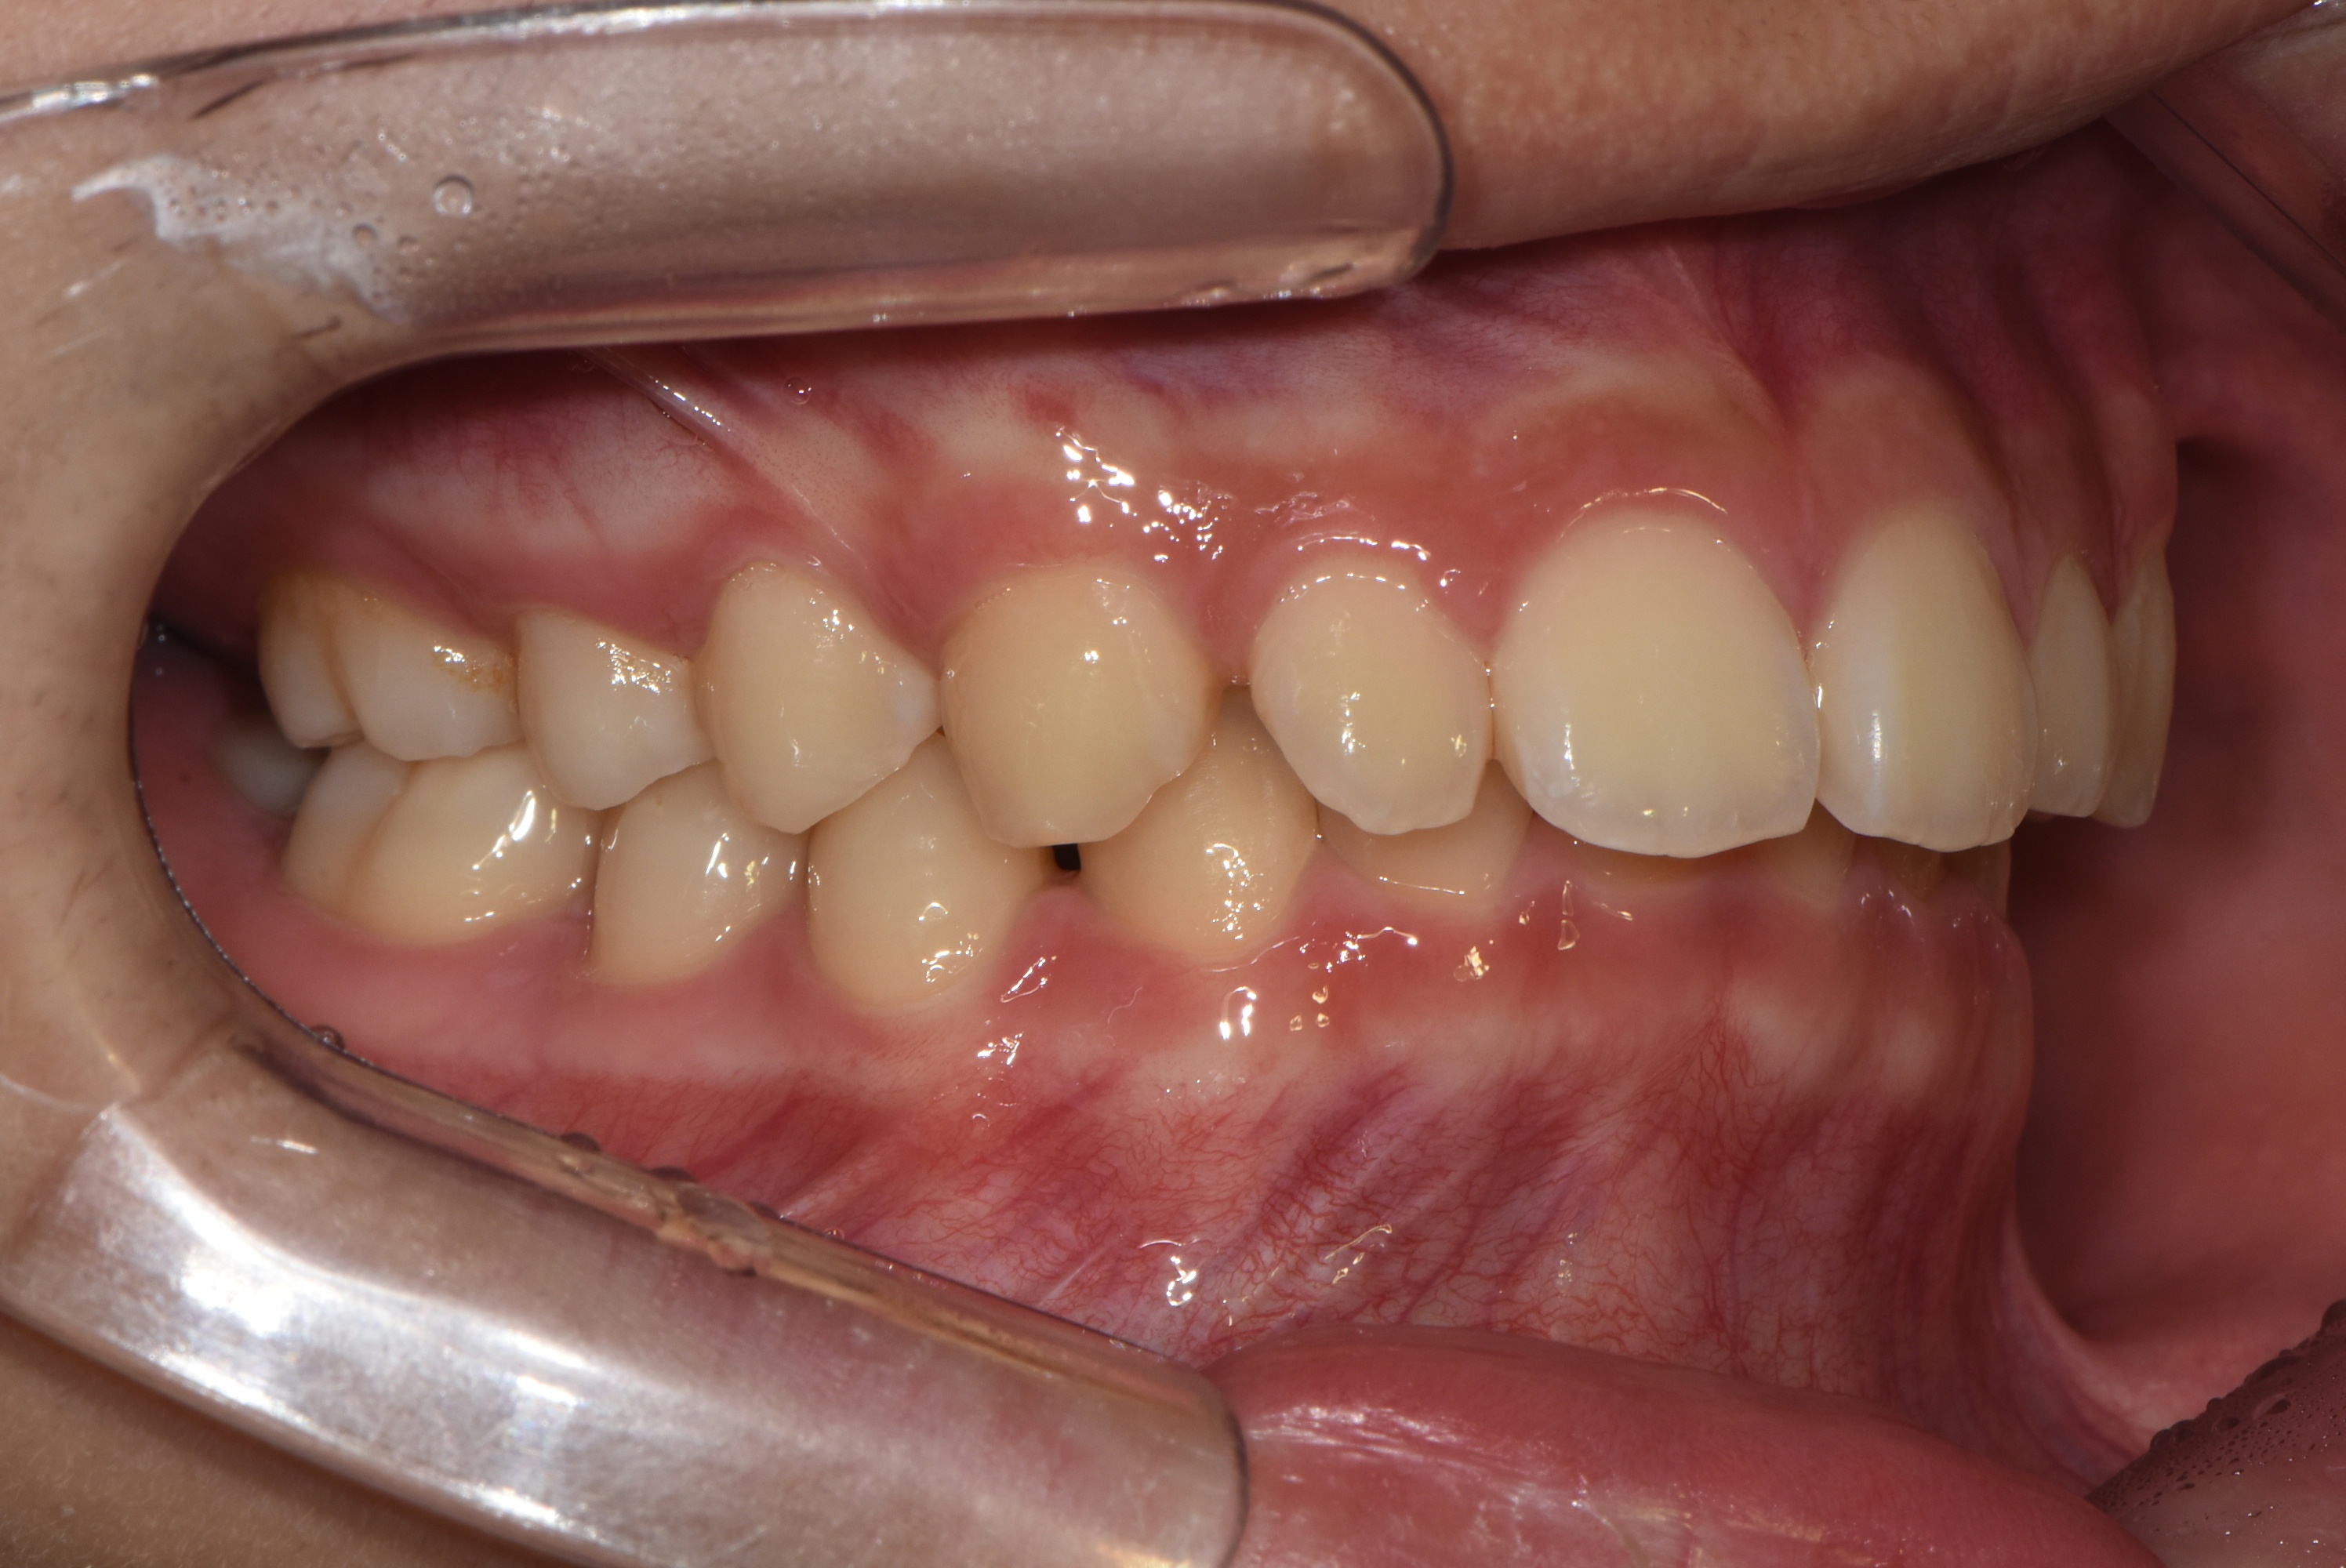

치료 전 사진입니다.